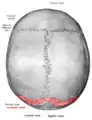

![]() Lambdoid suture (labeled at bottom right) | |

The lambdoid suture (or lambdoidal suture) is a dense, fibrous connective tissue joint on the posterior aspect of the skull that connects the parietal bones with the occipital bone. It is continuous with the occipitomastoid suture.

The lambdoid suture is between the paired parietal bones and the occipital bone of the skull. It runs from the asterion on each side.

The lambdoid suture is named due to its uppercase lambda-like shape.

Skull seen from behind. Showing Λ-like shape of the lambdoid suture.